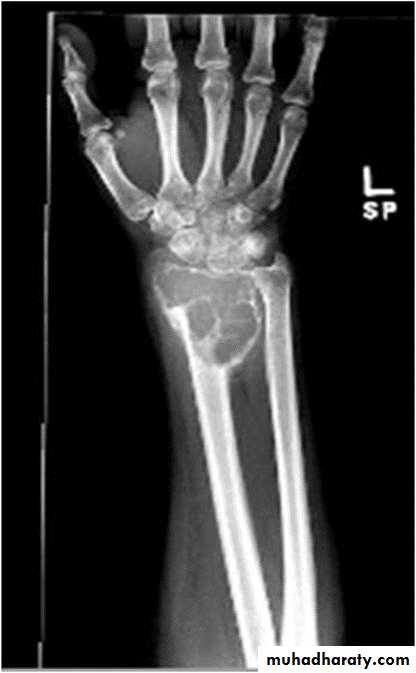

Giant cell tumor:Slowly growing , locally invasive, rarely metastasize.

Age: after closure of epiphysis (20-40 years).

Site: around knee & wrist joints.

Findings:

lytic, expansile lesion,

Sub articular in location,

Not clearly defined margin,

thinning of the cortex (sometimes with destruction of cortex)